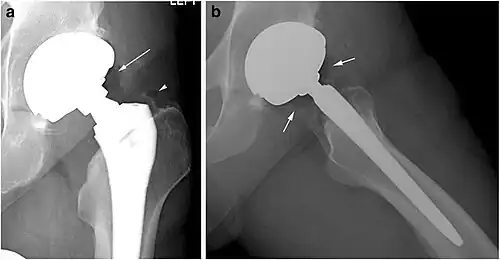

Pneumarthrosis is the presence of air in a joint. Its presentation on radiography is a radiolucent cleft often called a vacuum phenomenon, or vacuum sign.[7] Pneumarthrosis is associated with osteoarthritis and spondylosis.[8]

Pneumarthrosis is a common normal finding in shoulders[7] as well as in sternoclavicular joints.[9] It is believed to be a cause of the sounds of joint cracking.[8] It is also a common normal post-operative finding at least after spinal surgery.[10] Pneumarthrosis is extremely rare in conjunction with fluid or pus in a joint, and its presence can therefore practically exclude infection.[8]

X-ray of a hip with hip replacement and pneumarthrosis, in this case aseptic. -